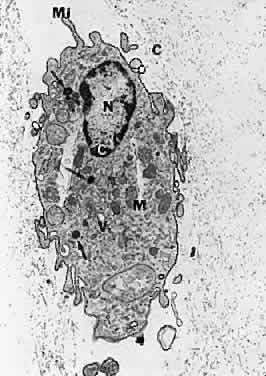

HYALOCYTES.

There are cells embedded within the posterior vitreous cortex (Fig. 18) known as hyalocytes. Situated 20 to 50 μm from the ILL of the retina, these mononuclear cells are widely spread apart in a single layer (Fig. 19). The highest density of hyalocytes is in the region of the vitreous base, followed by the posterior pole, with the lowest density at the equator. Derived from circulating monocytes and renewed every 6 months, hyalocytes are oval or spindle-shaped and are 10 to 15 μm in diameter. They contain a lobulated nucleus, a well-developed Golgi complex, smooth and rough endoplasmic reticula, many large periodic acid-Schiff-positive lysosomal granules, and phagosomes (Fig. 20). Balazs72 noted that hyalocytes are located in the region of highest HA concentration and suggested that these cells may be responsible for vitreous HA synthesis, which may also be true of vitreous collagen.

Fig. 20. Ultrastructure of human hyalocyte. A mononuclear cell is seen embedded within the dense collagen fibril (black C) network of the vitreous cortex. There is a lobulated nucleus (N) with a dense marginal chromatin (white C). In the cytoplasm, there are mithochondria (M), dense granules (arrows), vacuoles (V), and microvilli (Mi). (×11,670.) (Courtesy of Joe Craft and Dan Albert, MD)

The phagocytic capacity of hyalocytes derives from the presence of pinocytic vesicles, phagosomes (Fig. 20), and cell membrane receptors that bind immunoglobulin G (IgG) and complement. It is intriguing to consider that hyalocytes are among the first cells to be exposed to any migratory or mitogenic stimuli released during various disease states. Because hyalocytes are essentially tissue macrophages, they may have a role similar to macrophages in other diseases, i.e., to recruit cells and elicit further escalation of the inflammatory response. Whereas in some tissues this may be desirable, in the vitreous this process results in various untoward events, depending on the clinical circumstances. In the case of pars planitis, hyalocytes in the vitreous base may be responsible for antigen processing and eliciting an immune response typical of tissue macrophages that leads to the observed snow banks of inflammatory cells in the peripheral anterior vitreous. Indeed, for these and other reasons, this condition may be more aptly named peripheral anterior vitritis. After failed surgery for rhegmatogenous RD, hyalocytes are likely the first cells to participate in the formation of the contractile membranes that in PVR detach the retina again. The particularly high density of hyalocytes in the vitreous base may be important in the pathogenesis of anterior PVR, wherein the prominence of vitreous fibers also contributes to the disease process by facilitating cell migration and transmitting traction to the peripheral retina, ciliary body, and iris. Thus, the role of these cells must be adequately considered in defining the pathophysiology of PVR, perhaps leading to a new avenue for early intervention.